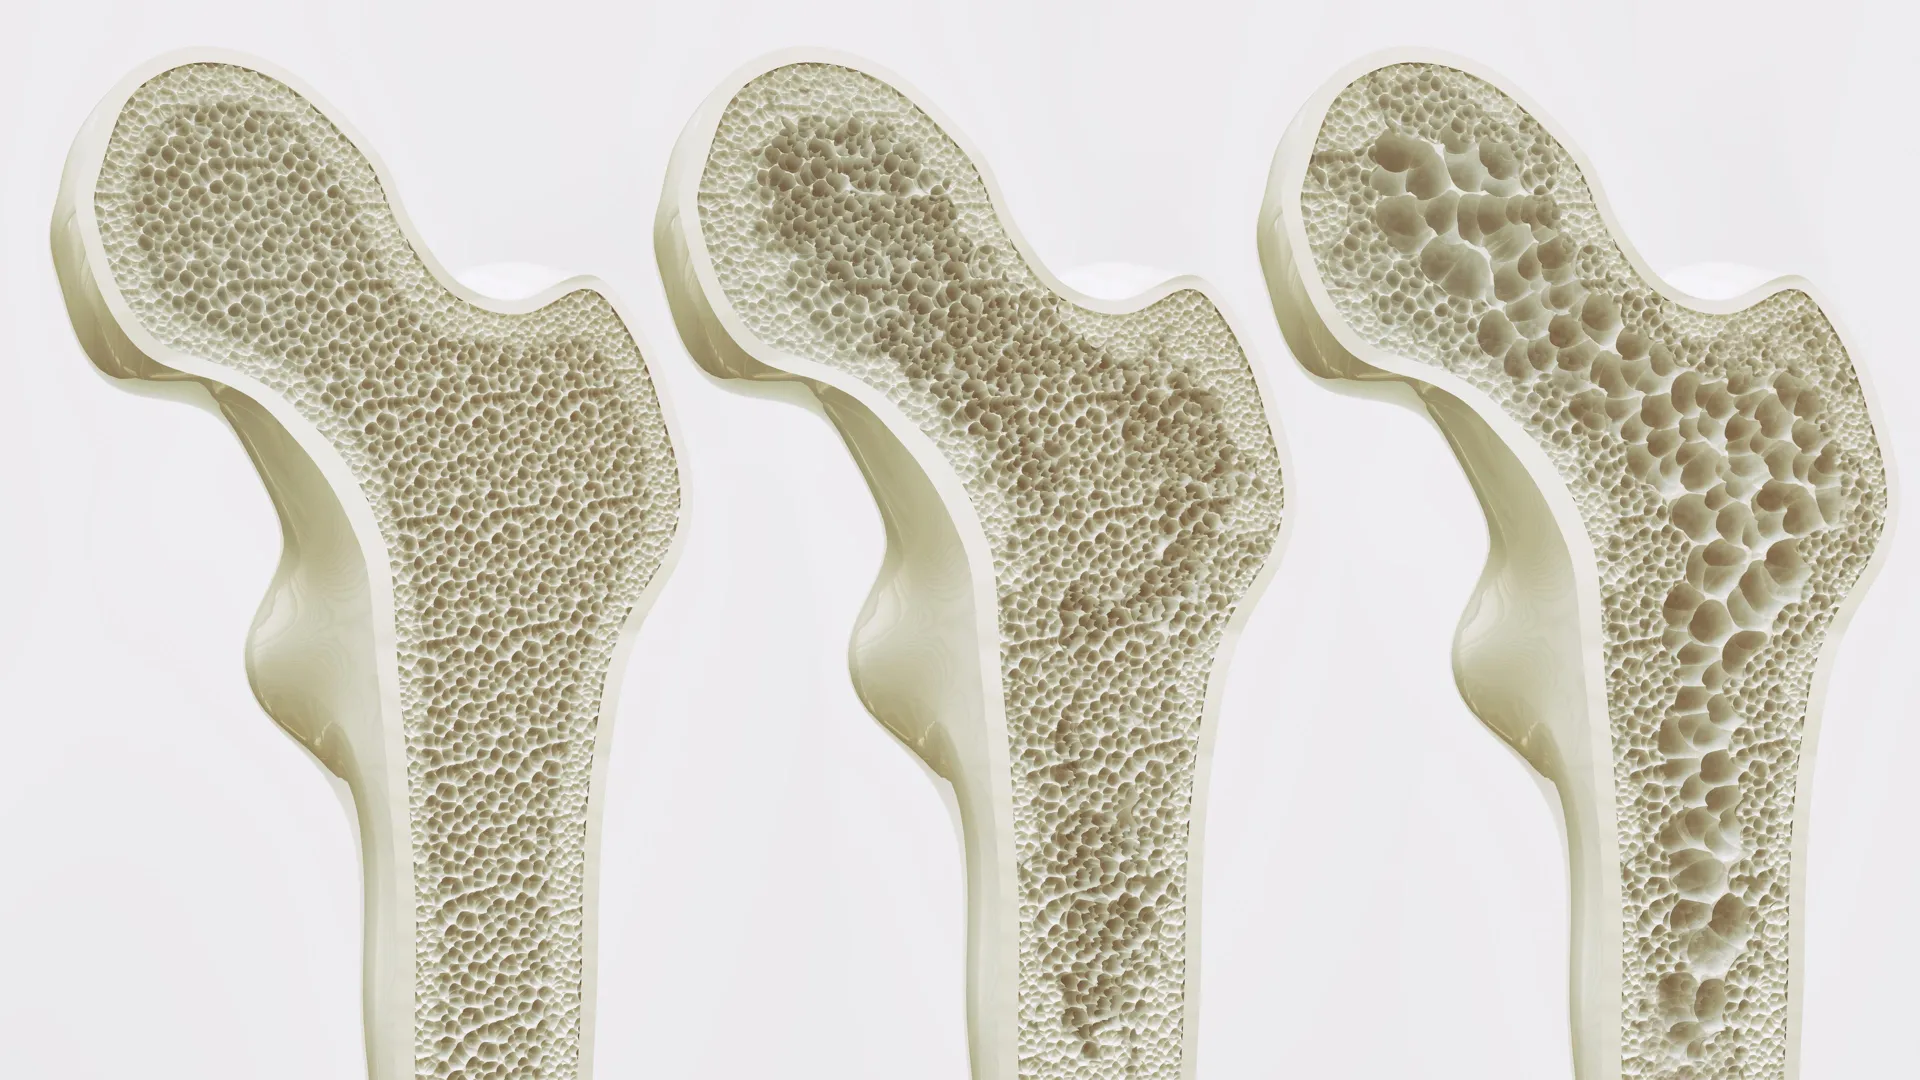

هناك طلب متزايد على العلاجات التي يمكن أن تمنع فقدان العظام وتعكسه بشكل آمن مع مرور الوقت. هشاشة العظام، وهي حالة تضعف العظام وتجعلها أكثر عرضة للكسر، تؤثر على حوالي ستة ملايين شخص في ألمانيا وحدها، معظمهم من النساء. وهو شائع بشكل خاص مع الشيخوخة وبعد انقطاع الطمث، عندما تنخفض كثافة العظام بشكل طبيعي.

قد يبدو العظم وكأنه بنية ثابتة، لكنه يتجدد باستمرار. يتحكم نوعان رئيسيان من الخلايا في هذه العملية. تكون الخلايا العظمية مسؤولة عن بناء العظام الجديدة، بينما تقوم الخلايا العظمية بتكسير العظام القديمة. تعتمد العظام الصحية على التوازن الدقيق بين هذين النشاطين.

غالبًا ما يطلق على هشاشة العظام اسم المرض الصامت لأن فقدان العظام يمكن أن يحدث دون أعراض ملحوظة حتى يحدث الكسر. بحلول الوقت الذي يتم اكتشافه، قد يكون قد حدث بالفعل ضرر كبير.

إن تحديد GPR133 كمنظم رئيسي لقوة العظام يفتح اتجاهًا جديدًا للعلاج. فبدلاً من إبطاء فقدان العظام فقط، يمكن للعلاجات المستقبلية إعادة بناء العظام واستعادة قوتها.